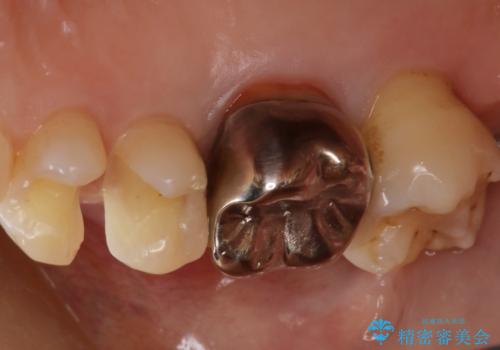

- 右上4、5の歯がしみるのを治したいという主訴で来院されました。精査の結果隣接面う蝕と診断し、適合がよく見ためも良いセラミックインレーでの治療を行いました。

セラミックインレーを入れた後は歯がしみることはなくなり、白く丈夫な被せ物が入り満足いただけました。